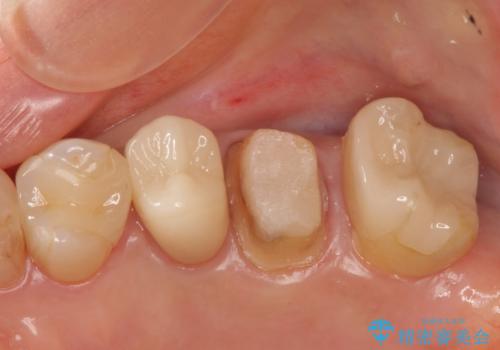

特に割れている所見はなかったため、根の治療から被せ物まで治療を行いました。

奥の銀歯のやりかえも希望されたため、セラミッククラウン、インレーにする治療をしています。

- 合計 48.4万円( 左上5:再根管治療 9万円、ファイバーコア2万円、仮歯1万円、ジルコニアクラウン10万円 左上6:仮歯、ジルコニアクラウン 左上7:emaxインレー7万円)費用は治療当時の料金となります